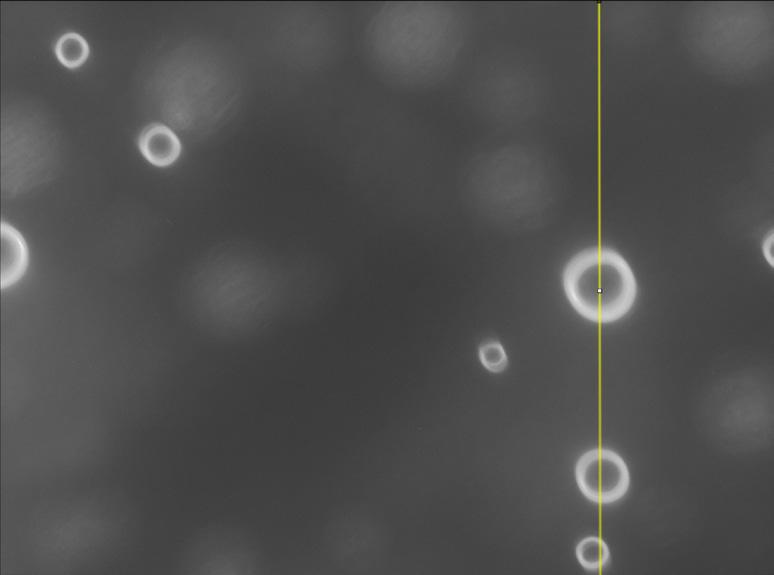

Scanning tunneling microscopy (STM) is the premier technique for atomic-scale imaging. Through preclinical and clinical studies, Acoustic Cluster Therapy (ACT) has demonstrated success in enhancing chemotherapy efficacy while reducing drug toxicity, compared to conventional passive transvascular drug delivery.[1][2][3] ACT consists of negatively charged microbubbles (Sonazoid™) and positively charged microdroplets, which form clusters via electrostatic interaction. These clusters, along with the administered drug, are activated by ultrasound to temporarily lodge in tumor capillaries, improving local drug delivery. However, the biomechanical mechanisms underlying ACTinduced enhancement of drug extravasation remain unexplored.

This study demonstrated a proof-of-concept imaging framework for detecting microbubbles and activated Acoustic Cluster Therapy (ACT) bubbles in tissue using reflectance microscopy. A customised imaging system enabled photometric stereo imaging. Optical clearing with 109.1 mM tartrazine (67 h, 8 rpm) improved light penetration and allows ability to observe the internal structure of the tissue and Sonazoid™ using confocal microscopy, while a 590 nm longpass filter provided subtle enhancement of bubble edge clarity. A multi-adaptive hough transform (mAHT) algorithm was developed for bubble detection. These approaches validated the combined use of photometric stereo, optical clearing, light filtering and algorithmic analysis. This integrated platform provides a foundation for future organ-on-a-chip studies aimed at understanding the biomechanical mechanisms of ACT-mediated drug delivery.

What was the aim of your project?

In this project, I aimed to carry out a proof-ofconcept study to assess the potential of three methods (photometric stereo, optical clearing with tartrazine and light filtering) and algorithms to improve ability to distinguish activated ACT microbubbles from surrounding tissue for eventual use in studying underlying biomechanical mechanisms of ACT.

Instead of traditional transmission microscopy, reflectance microscopy was implemented with a modified imaging system (shown in Figure 1)

Photometric Stereo was achieved by incorporating a ring light source, which through idealised ray diagram, shown as a reflected ring pattern from the specular bubbles.

What did you find out? Methods Validation

The combination of Photometric stereo and optical clearing results is promising with the ability to identify activated ACT bubbles within the ibidi µ-slide channel.

Bubbles at different depths of the channel were detected. The experiment was conducted with a 1000 µm thick tissue slice, which was compressed to 370 µm by the coverslip. However, the edges of the activated ACT bubbles were less well-defined compared with images obtained from thinner tissue slices.

Confocal Microscopy

Confocal Images were obtained using Zeiss LSM980/ Airyscan 2 Confocal Microscope. As shown in Figure 3, tartrazine-treated tissue slices exhibited enhanced visualisation of internal structures and stronger reflective signals corresponding to Sonazoid™ microbubbles (bright and clustered red dots). These results indicate that optical clearing

Figure 1.The basic setup of the microscope with main components labeled.

with 109.1 mM tartrazine improves light penetration and contrast in thick tissue samples, supporting the subsequent experiment using reflected incoherent light microscopy.

Figure 2. Images of identified activated ACT microbubbles in the tissue imaging setup of 1000 µm thick tissue slice using incoherent reflection imaging with the ring light source and optimal optical clearing without filtering. (a) top surface of ibidi µ-slide channel showing in-focus activated ACT bubbles (white arrows) and small bubbles (red arrows) (b) bottom surface of ibidi µ-slide channel showing activated ACT and smaller bubbles (white arrows).

Figure 3. Comparison of images of control and tartrazine treated tissue slices captured by Zeiss LSM980/Airyscan 2 Confocal Microscope. Grid of well plate (yellow arrow), Sonazoid™ (white arrows), large bubbles potentially air bubbles (blue arrows), and in-ternal tissue structure (red arrows). (a) 1000µm thick chicken breast tissue without tartrazine treatment. (b) 1000µm thick chicken breast tissue treated with Level A clear-ing experiment condition.